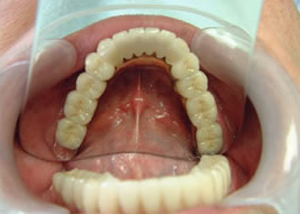

4.下14本最終の冠をかぶせたところ-上から(鏡)

-正面-下14本の最終の冠をかぶせたところ